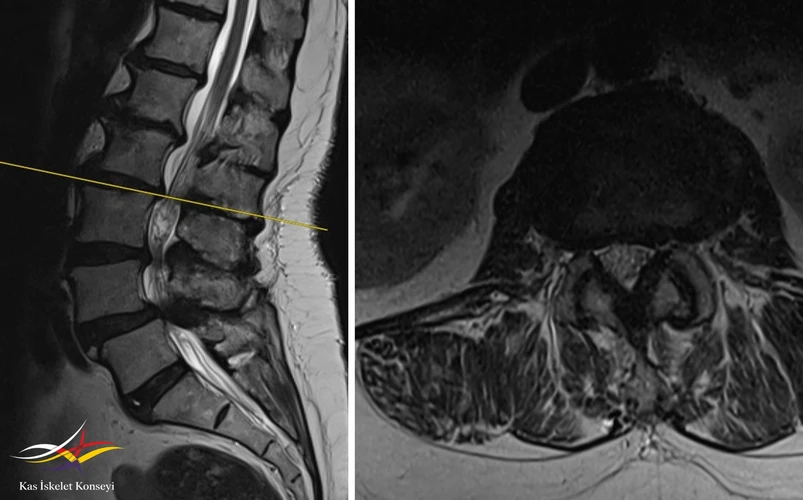

Resim 4. L3-4 seviyesinde belirgin bir kanal darlığı mevcut.